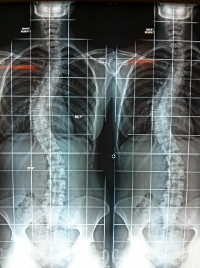

Scolioses

Généralités

Les scolioses de l'enfant (juvéniles)

Les scolioses de l'adolescent

Les scolioses de l'adulte